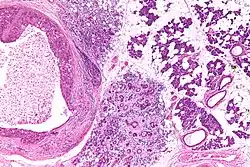

| Low magnification micrograph of a salivary duct carcinoma with characteristic comedonecrosis (left of image) adjacent to normal parotid gland (right of image). H&E stain. | |

Very low mag.

Very low mag. Intermed. mag.